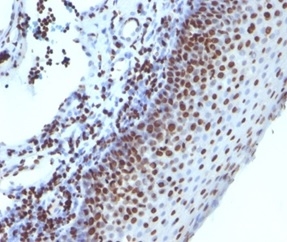

Immunohistochemistry (IHC)

1-2ug/ml

30 min at RT. Staining of formalin-fixed tissues requires heating tissue sections in 10mM Tris with 1mM EDTA, pH 9.0, for 45 min at 95°C followed by cooling at RT for 20 minutes

A-431, HeLa, LNCap or Jurkat cells. Human heart tissue lysate. Breast carcinoma.